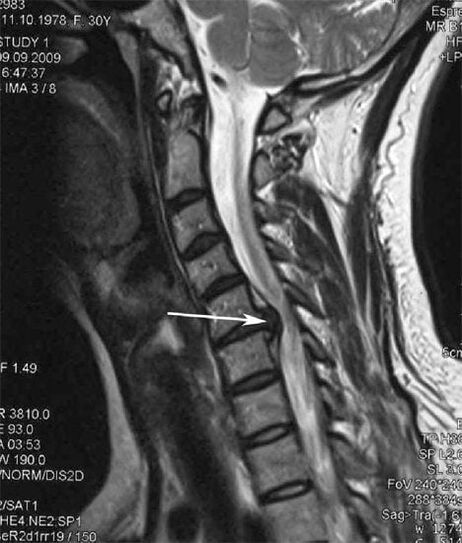

U početnim fazama osteokondroza se otkriva pomoću MRI. Kasnije se patologija može dijagnosticirati pomoću radiografije. Na rendgenskim snimkama vratne kralježnice uočava se smanjenje razmaka kralježaka, patološke promjene u fasetnim zglobovima i osteofitoza.

Mnogi se ljudi žale da ne mogu okrenuti vrat zbog jake boli koja se javlja nakon naglog podizanja nečega teškog. Ova pojava ukazuje na stvaranje hernije diska. Uzrok boli u leđima, vratu i gornjim udovima je uklještenje jednog od korijena živaca koji izlaze iz leđne moždine.